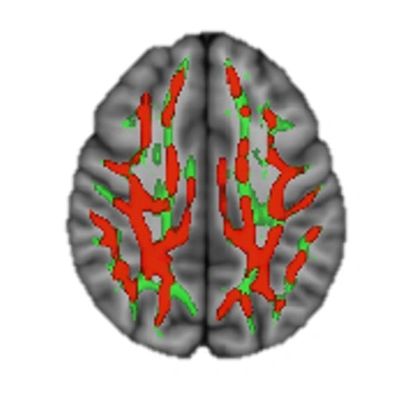

Comparison of Superior Cognitive Region of Brains

Red – significantly less damage in Xenon+SOC group

In a Phase 2 Clinical Study of 110 patients, published in JAMA, XENEX demonstrated significantly less brain damage than standard-of-care (SOC) alone in OHCA patients. The primary endpoint was reduction in cerebral white matter damage using MRI as a biomarker. Analysis of the global fractional anisotropy (GFA) measured the differences in diffusion of water in white matter tracts of brain to assess damage. The results were 42% less white matter damage, P=0.006. The primary endpoint of brain damage was the leading predictor of mortality at 6 months.